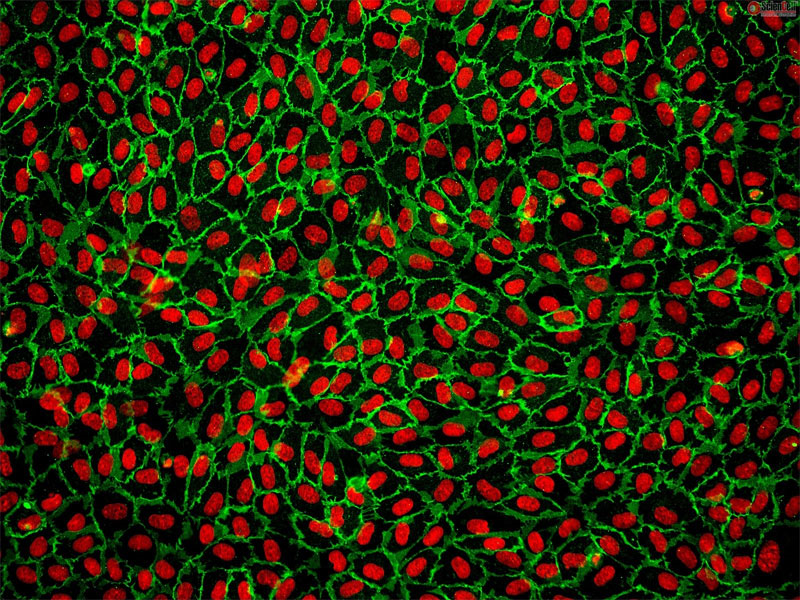

今回は例として,下記の画像に含まれる細胞の数をカウントするコードをVision Assistant上で作成していきます!

赤色の部分が細胞核,緑色の部分が細胞壁にあたりますので,細胞の数をカウントするに当たり画像内の赤色の細胞核がいくつ存在しているのかをカウントするコードを作成することを目標としたいと思います。

<今回使用する画像>

ヒト臍帯静脈内皮細胞 (HUVEC) CD31 の免疫蛍光染色画像(①)